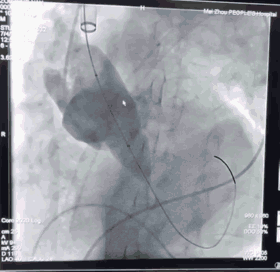

3228-200胸主动脉支架定位

胸主动脉支架释放后造影

由于患者年龄较大,主动脉严重缩窄合并主动脉瘤,主动脉结构较为脆弱,所以李存仁教授决定在胸主动脉覆膜支架植入后再对缩窄部位进行球扩。这样,已经植入的支架能够起到一定的保护作用,在支架的限制下,球囊既充分扩开了狭窄部位,又避免了过度扩张对主动脉造成的损伤。

使用球囊28mm*40mm扩张

植入弹簧圈进行填充封堵内漏

“一站式”手术完成